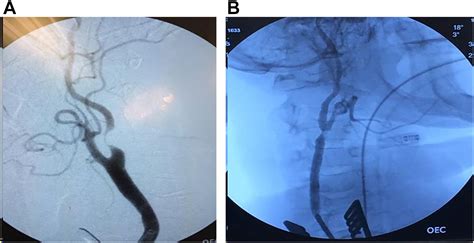

Transcarotid Artery Revascularization represents a paradigm shift in vascular surgery. Unlike conventional stenting, which requires navigating through the aorta—an area often riddled with debris that can break off and travel to the brain causing a stroke—TCAR accesses the carotid artery directly through a small incision at the neckline. By gaining direct access, surgeons can utilize a specialized system to temporarily reverse the flow of blood, moving it away from the brain while the stent is being placed. This unique feature acts as a safety net, capturing any potential plaque debris before it can cause neurological damage.

Because the procedure avoids the aortic arch, it is particularly beneficial for patients with complex anatomy or those whose health status might make traditional, more invasive surgeries too risky. The integration of neuro-protection during the stent placement is the primary reason why TCAR has seen such rapid adoption among vascular surgeons worldwide.

The success of Transcarotid Artery Revascularization lies in its precise clinical workflow. First, the patient is placed under light anesthesia. A small incision is made just above the collarbone. The surgeon places a specialized sheath directly into the carotid artery. The system is then connected to a flow reversal circuit, which safely diverts blood away from the brain and into a filter, which traps any loose particles. After the stent is securely placed and the artery is verified to be open and clear, the flow is returned to its normal path, and the small incision is closed.

The technical precision required for this procedure means it is performed by highly trained vascular surgeons. The ability to monitor the brain’s blood supply in real-time provides surgeons with peace of mind and patients with a higher degree of safety compared to procedures that don't employ flow reversal.